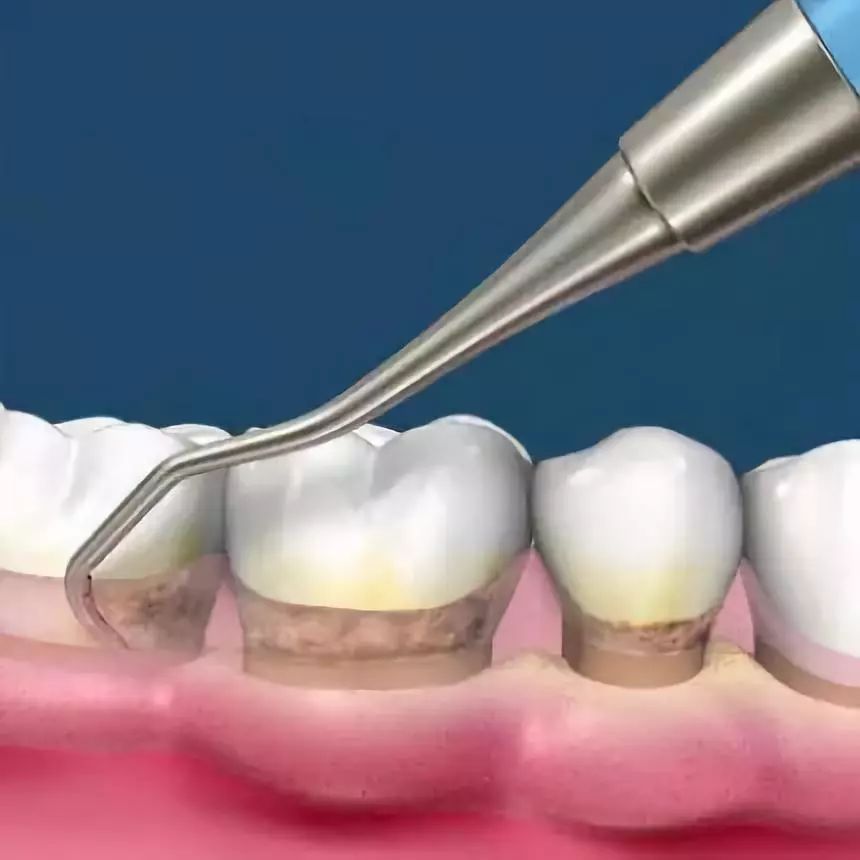

-超声波全口洁牙-

牙龈与牙根面之间不是紧密附着,而是存在一条0.5—2mm的浅沟,称龈沟。龈沟内易积存食物碎屑,附着菌斑,而且龈沟是难以彻底清洁的区域。

一般在刷牙之后的半小时内即会有新的菌斑形成,久而久之即成为牙结石,这些细菌会引起牙龈炎、牙周炎、出血、口臭,最终引起牙齿松动,甚至脱落。

而洗牙,是借由各种器械来去除这些附着于齿颈与牙龈沟之间的牙结石及牙菌斑,可以减轻牙龈炎、牙周炎的炎症状况。